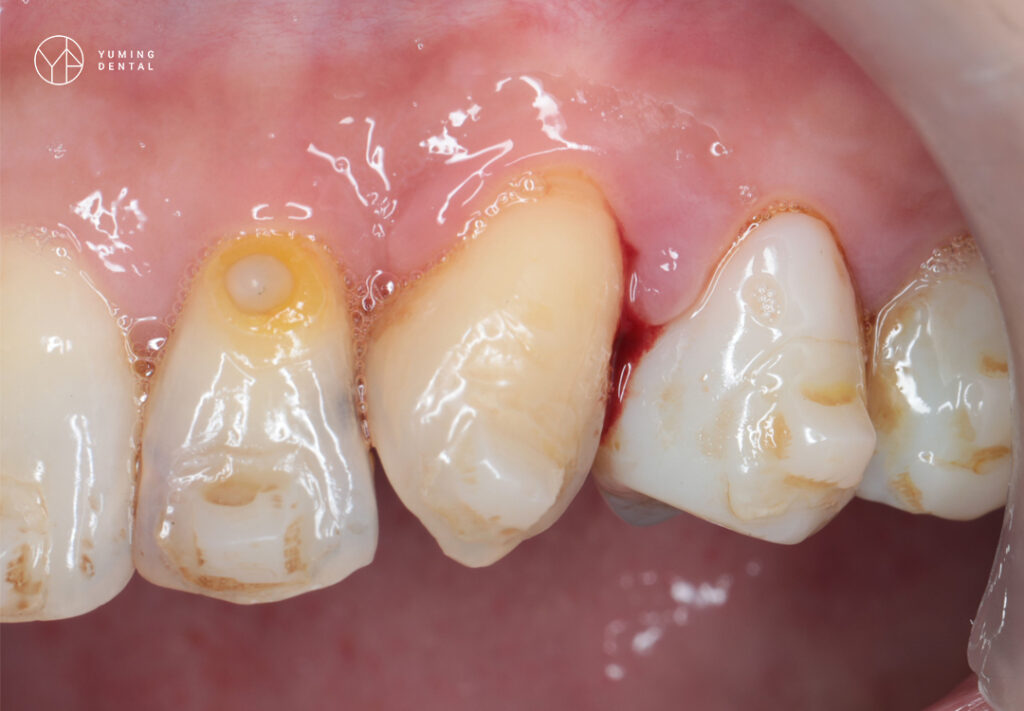

當牙齒內部(牙髓腔)或牙齒周圍(牙周組織)受到細菌侵襲,大量的白血球會前往聚集對抗感染。在發炎反應過程中,死亡的白血球、細菌殘骸與組織液混合形成「膿液」。由於口腔骨頭與牙齦組織緻密,膿液無處宣洩,便會尋找阻力最小的路徑(通常是牙齦表面)穿出,形成外觀可見的紅腫凸起,觸感類似充滿液體的小水球。

並非所有膿包都一樣,臨床上醫師會依據「感染源頭」將其分為三類,這直接決定了治療計畫的方向:

(1)牙根尖膿腫(Periapical Abscess):

成因: 通常源於未治療的深度蛀牙,細菌侵入牙髓神經導致壞死,感染向下蔓延至牙根尖端,並穿破骨頭在牙齦形成開口(瘻管)。

位置: 多位於牙齦較深處(靠近牙根底部)。

(2)牙周膿腫(Periodontal Abscess):

成因: 源於嚴重的牙周病。牙結石堆積導致牙齦與牙齒分離,形成深邃的「牙周囊袋」。當囊袋開口阻塞,內部細菌大量繁殖化膿。

位置: 多位於牙齦邊緣或牙縫間的牙齦乳頭。